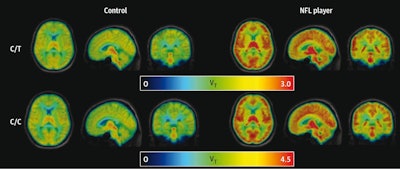

Mean parametric maps of carbon-11 (C-11) DPA-713 radiotracer binding (VT) are presented in three views for each group (NFL, control) within each TSPO genotype (C/C, C/T). VT indicates total distribution volume and is in units of milliliters per cubic centimeter (mL/cm3). Image courtesy of JAMA Network Open.

According to the findings, the magnitude of the group differences depended on brain region, with largest differences in total TSPO distribution volumes on PET seen in the cingulate and frontal cortices as well as the hippocampus.